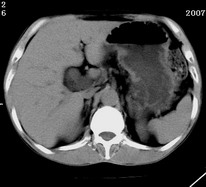

以下是引用zjzjr在2007-9-15 22:24:00的发言:[br]胰头钩突略饱满,肝内外胆管略扩张,胆囊积水.建议增强扫描.

以下是引用代课学生在2007-9-16 10:20:00的发言:[br]胆总管中段以上胆管均示扩张,考虑胆总管下段/胰头部病变,建议增强或micp检查。